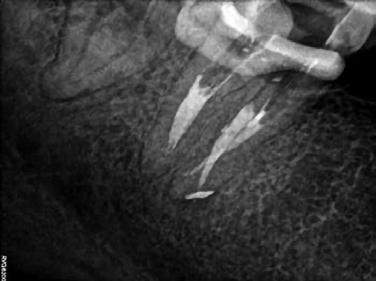

Egy 40 éves hölgy pácienst a jobb alsó második nagyőrlőfogának (47) panaszossága és kopogtatáskor jelentkező érzékenysége miatt irányították dr. Karaś rendelőjébe. A hagyományos technikával készített röntgenfelvételeken a beküldő orvos nem észlelt gyökércsatornák jelenlétére utaló jeleket, ezért úgy gondolta, hogy a fog endodonciai ellátása túlmutat saját kompetenciakörén.

Az első vizsgálat során CBCT-felvétel készült. A felvételen egy kis méretű radiolucens elváltozást észleltünk a mesialis gyökércsúcs körül. Ez alapján azt vélelmeztük, hogy elérhető lehet a mesialis gyökércsatornák átjárhatóságának biztosítása. A disztális gyökér körül nem láttunk gyulladásra utaló jeleket, így a panaszok hátterében valószínűleg a mesialis gyökér végén látható gyulladásos elváltozás állt. További leletként a mesio-bukkális gyökércsatornában (MB) egy törött lentulót is észleltünk (16. a–b ábra).

Az első kezelés célja a törött eszköz eltávolítása és a gyökércsatornák átjárhatóságának biztosítása volt. Helyi érzéstelenítés és a kofferdám felhelyezését követően a meglévő tömés eltávolításra került. Ezt követően láthatóvá vált, hogy mindhárom gyökércsatorna-bemeneti nyílást Endomethasone N fedi. Ezt az anyagot ultrahangos fej (U-file) és 5,25%os NaOCl alkalmazása révén távolítottuk el. Ezután a lentuló is láthatóvá vált. Sajnálatos módon a lentuló nem cementbe volt ágyazva, hanem a gyökércsatorna görbülete mögött egy fel nem tágított gyökércsatornafal-szakaszba ékelődött be. A tört részt kalcifikálódott szövetek borították. Ez alapján azt vélelmezzük, hogy az első kezelés során ezt a gyökércsatorna-szakaszt még élő fogbél töltötte ki. Ekkor azt a döntést hoztuk, hogy a kalcifikálódott szöveteket 10-15 percen keresztül végzett lézerrel aktivált folyamatos 5,25% NaOCl átöblítéssel megpróbáljuk eltávolítani. A terv sikeres volt, a

betört eszköz és a kalcifikálódott szövetek is eltávolításra kerültek. A betört műszer egészben történő eltávolításáról kontrollröntgen segítségével győződtünk meg (17. ábra)

A páciens öklendezése miatt a beavatkozások nehezen voltak elvégezhetőek. A kontrollröntgen elkészítése után a csatornát AutoSWEEPS módban alkalmazott SkyPulse lézerrel aktivált 17%-os EDTA és 5,25% NaOCl oldattal átöblítettük. A lézert néhány 15-20 másodperces ciklus idejére alkalmaztuk, majd a csatorna átjárhatóságát kézi tű segítségével ellenőriztük. Ekkor egy újabb kontrollröntgen készült, amely azt mutatta, hogy a tűnkkel az előzőleg elkészített gyökértömés végénél mélyebbre jutottunk (18. ábra). Ezután a fogat egy kompozitból készült ideiglenes töméssel zártuk, majd visszarendeltük egy következő időpontra.